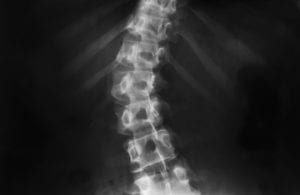

In scoliosis, the spine takes on a curved shape like an “S” or a “C.” It usually develops after a child undergoes a growth spurt. Mild scoliosis may not cause any problems during the patient’s lifetime. However, if the spinal curvature is moderate to severe, it can cause back pain, disability, and difficulty in breathing…

Scoliosis is a condition characterized by an abnormal curvature of the spine: instead of falling into normal alignment, the vertebrae make an S- or C-shaped curve. Over time, the curve may become more prominent and eventually cause health problems. There are four types of scoliosis: idiopathic, neuromuscular, degenerative, and congenital scoliosis. While these types have…

Scoliosis is a complex disorder in which the spine forms an unusual curve, often in a somewhat “S” shape or a “C” shape. It can occur in both children and adults, but it is usually discovered in childhood. Classic scoliosis characteristics and symptoms include the following: Curved spine Uneven shoulders, hips, and/or waist Back…

Scoliosis is a spine disorder that creates an abnormal curvature, or twisting, of the spine. It can affect people of any age, but it commonly occurs in children between the ages of 10 and 15. Some cases of scoliosis have clear causes, but most cases do not. A healthy spine is vertically straight when looking…